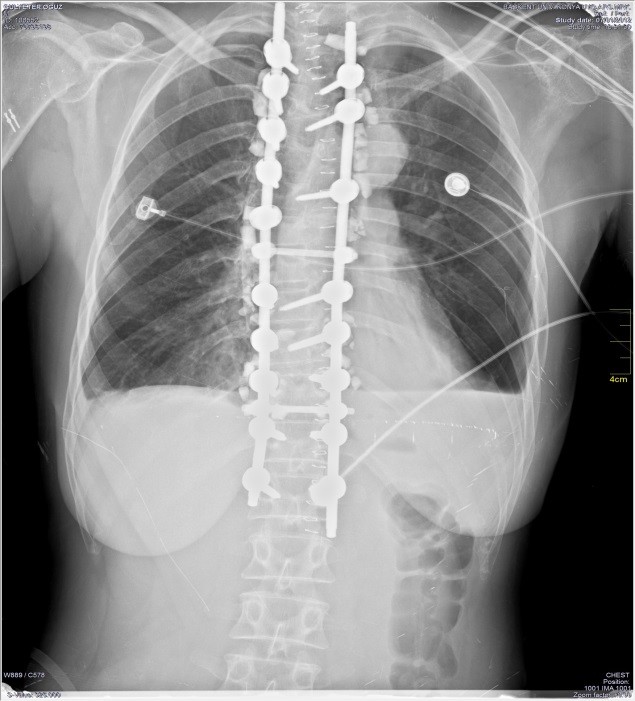

Sonuçta omurga cerrahisinde yaradılıştan gelen vücut yapısına dışardan yerleştirilen enstrumantlar konulmaktadır.

Bu enstrumantların sayısı ve türü var olan soruna göre değişmektedir. Bu enstrumanatların vucuda uyum sağlaması gereklidir. Örneğin bir diş dolgusunda bile alışma süresinin olması gibi. Enstrumantların vucuda alışma süresi 6 ayla 1 yıl arasında değişmektedir.

3.Düştüm platinlerim kayar, kırılır endişesi: Usulüne uygun yerleştirilmiş platinlerin küçük haretlerle kayması ve kırılması mümkün

değildir. Ancak yaşlı hastalarda ilerleyen kemik erimesi söz konusu olduğunda platinlerde hareketlenme gelişebilir. Ağır kazalarda

veya darbelerde platinlerde kırılma olabilir. Bilindiği üzere her maddenin belirli bir dayanma gücü vardır. Süre geçtikçe metaller yorulur.

Buna metal yorgunluğu adı verilir.

4.Belime takılan platinlerin belirli bir süreden sonra alınması gerekliymiş: Belinize koyulan enstrumantlar vucüt tarafından kabul edilen

malzemelerdir. Sizde var olması sakınca oluşturmaz. Ancak gerek hastanın psikolojik yapısı enstrumantların varlığına izin vermiyorsa

gerekse var olam sorun kemiklerle güçlendirilmişse 2 yıldan sonra platinler alınabilir.

5.Platinli operasyondan sonra yine aynı sorunlar gelişebilir mi? Belinize koyulan enstrumantlar belirli bir segmenti kontrol altında tutar

ancak bu segmentlerin üzerindeki ve altındaki segmentler için koruma sağlamaz. Yani hasta olarak tarafınızın bu tür ameliyatlardan

1. Vidaların malpozisyonu: yani vidaların uygun yere yerleştirilememesi. Yani vidaların omurga içinde değil etrafında yerleşim

göstermesi.Tekrar ameliyat riski taşır

1.Vidaların yerinden kayması genellikle nedeni zaman içinde gelişen osteoforz veya şiddetli travmalardır.

2.Vidaların kırılması Metal yorguluğuna veya seviyesine uygun kalınlıkta vida yerleştirilmemesine veya enstrumant sisteminin kalitesine

bağlıdır.

3.Rodların yerinden kayması Vidaları bağlayan sistemlerin metal yorgunluğuna, travmalara veya sistemin kalitesine bağlıdır.